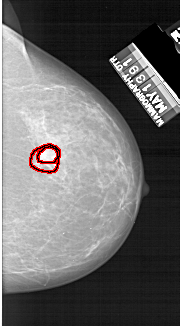

FILE: A_1134_1.RIGHT_CC.OVERLAY

TOTAL_ABNORMALITIES 1

ABNORMALITY 1

LESION_TYPE MASS SHAPE IRREGULAR MARGINS SPICULATED

ASSESSMENT 4

SUBTLETY 4

PATHOLOGY MALIGNANT

TOTAL_OUTLINES 2

BOUNDARY

CORE